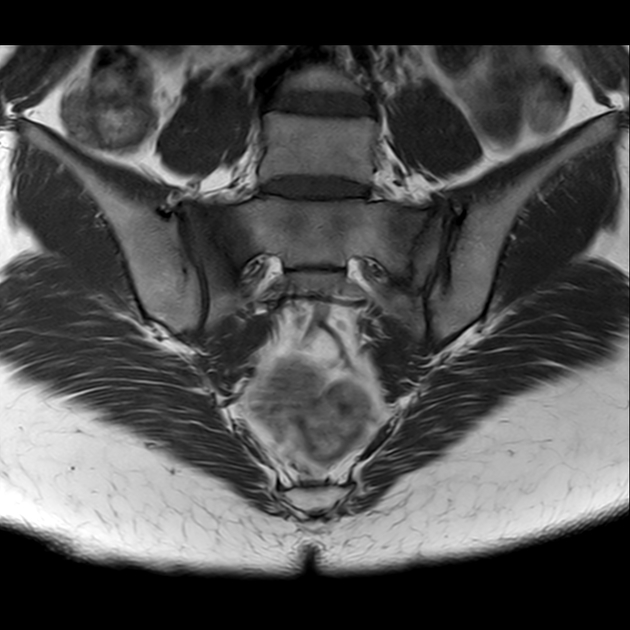

磁共振检查:

T2

影像表现

2、单侧或双侧骶骨翼骨皮质断裂,见迂曲纵行骨折线,大致与骶髂关节平行(双侧多见);

3、骶骨体部看见骨折线

4、冠状位上述骨折形成 “H”型 ,故有人称东风本田征(为了方便记忆)

5、骨折线一般较为模糊,看见看到骨质硬化;

6、磁共振上可以发现骨折线周边明显的骨髓水肿,增强扫描明显强化

磁共振影像表现